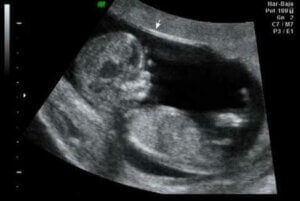

임신 12주차의 초음파

이는 임신 첫 분기의 전환점으로 12주가 첫 번째 초음파를 하기에 이상적인 시간이 될 수 있다. 이를 통해 장기가 올바르게 발달하고 있는지 확인할 수 있다.

또한, 아기의 크기와 몸무게는 물론 모든 태아의 목덜미에 있는 액체인 목덜미 투명대의 존재 여부를 확인할 수 있다.

“전문가들이 태아에게 존재할 수 있는 기형의 60~70%가 이 시점에서 이미 발견될 수 있다고 주장하는 것을 고려할 때, 이는 중대한 시기가 아닐 수 없다.”

다른 한편, 이 시기에 태아의 목덜미 너비를 측정한다. 이 수치는 첫 삼 분기 검진의 일부로, 염색체 수(이수성으로 알려진)의 기형, 특히 3염색체성 21 또는 다운 증후군의 위험을 감지할 수 있다. 이는 이러한 데이터와 다음을 포함한 다른 연구 간의 관계 덕분에 가능하다.

- 엄마의 나이

- 호르몬 값

- 목덜미의 반투명도 값

태아 기형의 60~70%가 첫 번째 초음파에서 발견될 수 있다.

태아의 첫 움직임을 알아차리는 것 외에도 흥미로운 부분은 출산 예정일을 추정하는 것이다. 이 예정일은 단지 5%만이 정확하다.